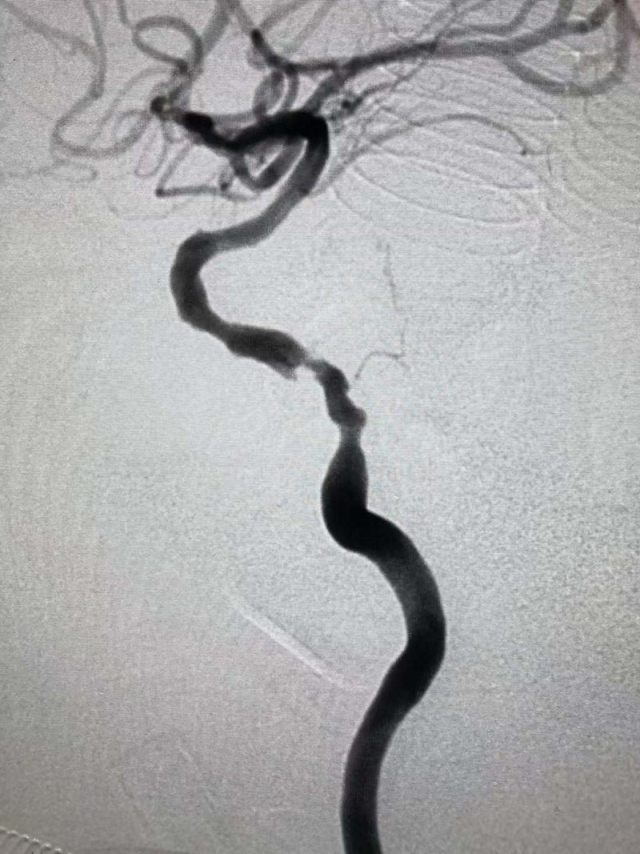

接诊后,敖主任完善患者相关检查,给予患者行脑血管造影检查显示:患者左侧颈内动脉颅内段重度狭窄(狭窄率达 80%),右侧颈动脉起始部狭窄(狭窄率达 70%),若左侧颈内动脉颅内段狭窄进一步加重,有可能会导致血管急性闭塞,这不仅意味着患者将面临终身瘫痪,甚至随时会有生命危险!

为了挽救患者生命,敖主任及科室骨干全力制定治疗方案,及时向患者及家属告知病情,完善相关术前检查,患者无禁忌症,组织相关人员进行了术前讨论,最终于 8 月 17 日下午,在李院长的指导下,兄弟科室全力配合下,首次独立成功完成了颈动脉颅内段支架植入术,术中、术后患者未诉不适,目前已康复出院。